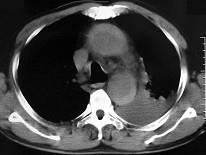

问题 男,58岁,有高血压病史,突发胸背剧痛,CT扫描如图,其最可能的诊断为 ( )

选项 A、高安氏病 B、主动脉夹层动脉瘤 C、主动脉假性动脉瘤 D、主动脉窦瘤破裂 E、主动脉瘤

答案 B